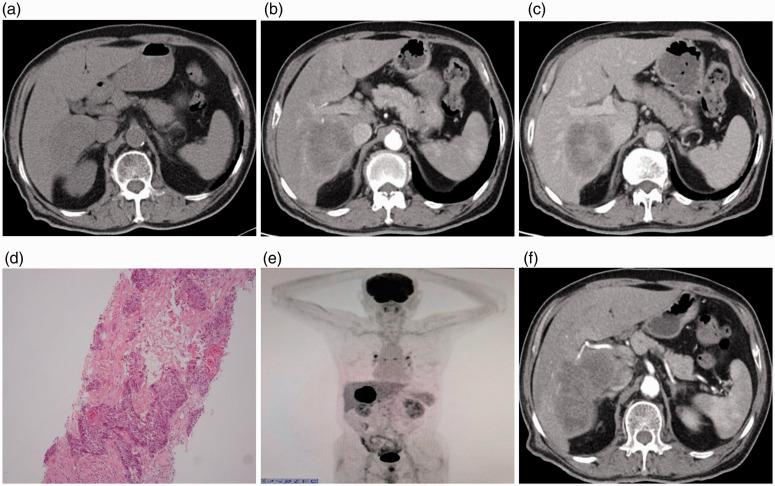

Primary squamous cell carcinoma of the liver is extremely rare, very difficult to diagnose, and carries an extremely poor prognosis. In this study, we discuss the imaging features of a patient with primary hepatic squamous cell carcinoma. The patient was admitted to hospital owing to discomfort in the right upper abdominal quadrant and a loss of appetite. He had no previous risk factors associated with hepatic squamous cell carcinoma and no history of systemic squamous cell carcinoma. We diagnosed primary hepatic squamous cell carcinoma by pathological analysis. Primary hepatic squamous cell carcinoma is rare, and its histological features are controversial, which makes the clinical and imaging diagnosis difficult. Therefore, it is urgent to improve the understanding of this disease in clinical practice to avoid misdiagnosis, and to identify the best treatment. This case provides a basis for the clinical diagnosis of primary hepatic squamous cell carcinoma.

原发性肝鳞状细胞癌极为罕见,极难诊断,预后极差。本研究讨论了 1 例原发性肝鳞状细胞癌患者的影像学特征。该患者因右上腹不适和食欲不振而入院。他没有与肝鳞状细胞癌相关的既往风险因素,也没有系统性鳞状细胞癌的病史。我们通过病理分析诊断为原发性肝鳞状细胞癌。原发性肝鳞状细胞癌罕见,其组织学特征存在争议,这使得临床和影像学诊断困难。因此,迫切需要提高对该疾病的认识,避免误诊,并确定最佳治疗方法。本病例为原发性肝鳞状细胞癌的临床诊断提供了依据。